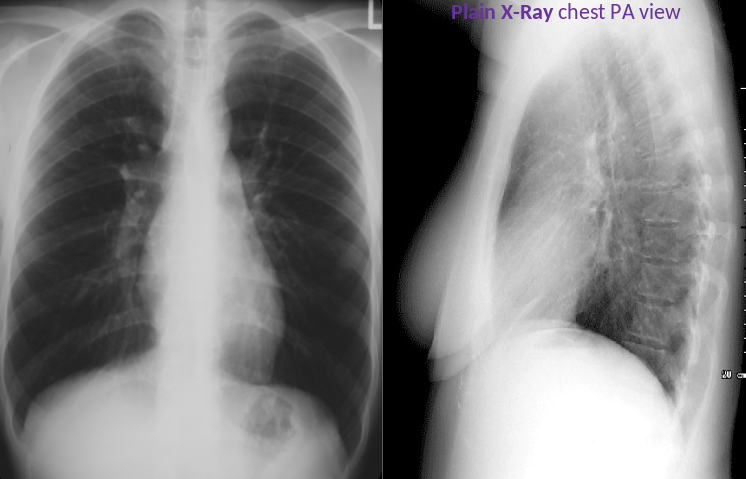

X-ray chest (PA view)

Lungs : The lung volumes are normal. No abnormal pulmonary parenchymal opacities are seen.

Mediastinum :Superior mediastinum are normal in size and configuration.

Costophrenic angles: The lateral costophrenic sulci (outlined in green) are sharp, with no evidence of effusion.

Bone & soft tissue : No concerning skeletal lesions are identified.